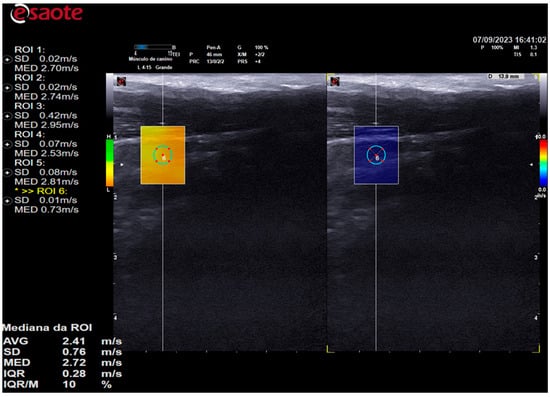

Elastographic images were obtained in the longitudinal plane of each thyroid lobe, and a scale of 0.0 to 10.0 m/s was employed in all cases. Once the thyroid lobe was properly framed in the image, the QelaXtoTM 2D software quality map was initiated. The map indicated the most suitable locations for acquiring shear-wave velocity. These were colored green to indicate high quality (Figure 3), yellow to indicate medium quality, and orange to indicate low quality (Figure 4).

Figure 4. The image on the left is a two-dimensional shear-wave elastography image of the left thyroid lobe of a 3-year-old female dog. The elastographic image on the left shows the quality map from the QelaXtoTM 2D software, which is colored orange. This indicates that the quality is low for measuring shear-wave velocity (quantitative). The right side of the elastographic image displays a colored elastogram (qualitative) from the QelaXtoTM 2D software, colored in blue, indicating that the thyroid parenchyma exhibited low stiffness (soft).